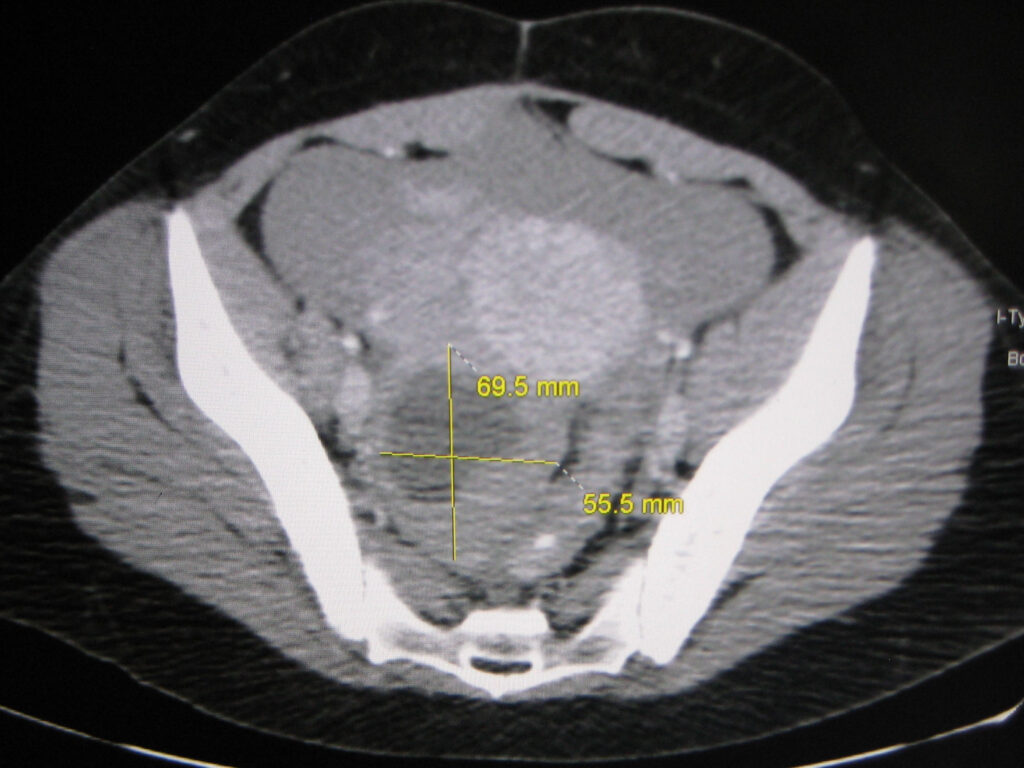

Upon presentation to a medical facility, diagnostic steps typically include a pelvic exam and ultrasound to confirm the rupture and assess any associated bleeding. In certain cases, a CT scan may also be utilized to gain a more detailed view of the abdominal cavity. For postmenopausal patients, a CA-125 blood test might be conducted to rule out potential malignancy, given that symptoms can sometimes overlap.

One primary factor is the cyst’s sheer size and the pressure it exerts on surrounding structures. When cysts grow larger than 10 cm, their increased mass can begin to compress nearby organs and tissues, including sensitive pelvic nerves like the sciatic nerves or the ureters. This persistent compression often results in pain that radiates into the lower back, potentially becoming chronic and debilitating.

This significant pressure can also lead to secondary complications, such as urinary retention if the bladder is heavily compressed, or chronic constipation if the intestines are affected. Monitoring symptoms like persistent pelvic fullness or bloating can help identify problematic cysts early. Early detection through advanced imaging techniques, such as MRI, is often crucial in preventing these more severe, long-term issues.